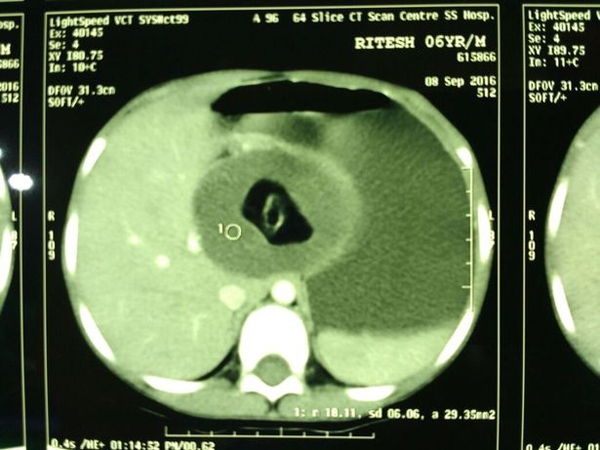

20/09/2016 15:43Bào thai song sinh trong bụng bé trai 6 tuổi

Các bác sĩ bất ngờ khi khối u mà họ định cắt bỏ khỏi bụng cậu bé thực chất là bào thai song sinh đã có đủ tay, chân, tóc.

Sau 3 tháng thăm khám vẫn không có kết quả, hôm 15/9 bố mẹ Ritesh quyết định cho con trai vào một bệnh viện tư nhân, nơi kết quả siêu âm cho thấy có một "khối u" trong ổ bụng em. Một nhóm gồm 5 bác sĩ đã lập tức tiến hành phẫu thuật cho cậu bé để loại bỏ khối u này.

Tuy nhiên, sau 3 tiếng phẫu thuật, các bác sĩ bất ngờ khi nhận ra cái u kia thực chất là phôi thai không phát triển đầy đủ, cũng là người em song sinh của Ritesh. Bào thai đã sống trong cơ thể cậu bé từ khi em chào đời.

| Hình chụp siêu âm cho thấy bào thai trong bụng bệnh nhân. Ảnh: Barcroft |

Theo Pradesh, bào thai đã có đủ tay, chân và tóc. Alok Bhardwaj, một bác sĩ nhi lâu năm, sau đó cho hay đây là trường hợp "hiếm nhất trong số những trường hợp hiếm" mà ông từng gặp. Tuy nhiên hiện vấn đề của cậu bé đã được xử lý thành công.

"Tình trạng cậu bé đang hoàn toàn ổn định và cũng phục hồi khá nhanh. Nếu không được phát hiện loại bỏ sớm, bào thai sẽ gây ảnh hưởng nghiêm trọng đến bệnh nhân trong tương lai", ông Bhardwaj nói.